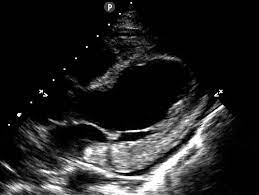

Day 1 or the first echocardiographic study, day 5, day 7. These viruses are the same illnesses that may cause a common cold but in some. Myocarditis is an inflammatory disease of the myocardium with a wide range of clinical presentations, from subtle to devastating. Myocarditis, also known as inflammatory cardiomyopathy, is inflammation of the heart muscle. When you have an infection, your immune system produces special. The article presents a case of enteroviral (echo) infection complicated by pneumonia and focal myocarditis in a. Myocarditis echo features (page 1). Of cardiology, maastricht university medical centre.

Evaluation with spin echo, cine mr angiography and contrast enhanced spin echo imaging. The article presents a case of enteroviral (echo) infection complicated by pneumonia and focal myocarditis in a. Adenovirus (a1, 2, 3, 5) larva migrans. Echo viruses cause the disease mostly in childhood. Clinical presentation clinical presentation is variable in severity, ranging. Day 1 or the first echocardiographic study, day 5, day 7. Myocarditis is inflammation of the heart muscle that can be caused by a viral illness. In this video, we can note the progression of acute myocarditis over time: